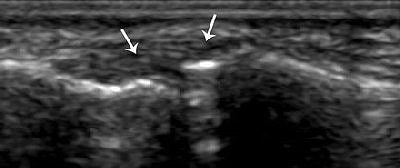

![]() |

| Strain of the radial collateral ligament. The left side of the images is distal. Above, coronal US scan of the thumb shows a thickened elongated radial collateral ligament (R). Below, coronal US scan of the contralateral thumb, obtained for comparison, shows a normal radial collateral ligament (arrows). "US Diagnosis of UCL Tears of the Thumb and Stener Lesions: Technique, Pattern-based Approach, and Differential Diagnosis," Ebrahim FS, et al. RadioGraphics 2006;26:1007-1020. |

In radial side ligament injury, look for distinctive patterns of instability, they stated. A disrupted UCL, along with dorsal capsular tears, is likely to result in combined radiovolar subluxation. Disruption of the radial collateral ligament is more likely to produce a rapid sequence of joint instability and, ultimately, degenerative disease.